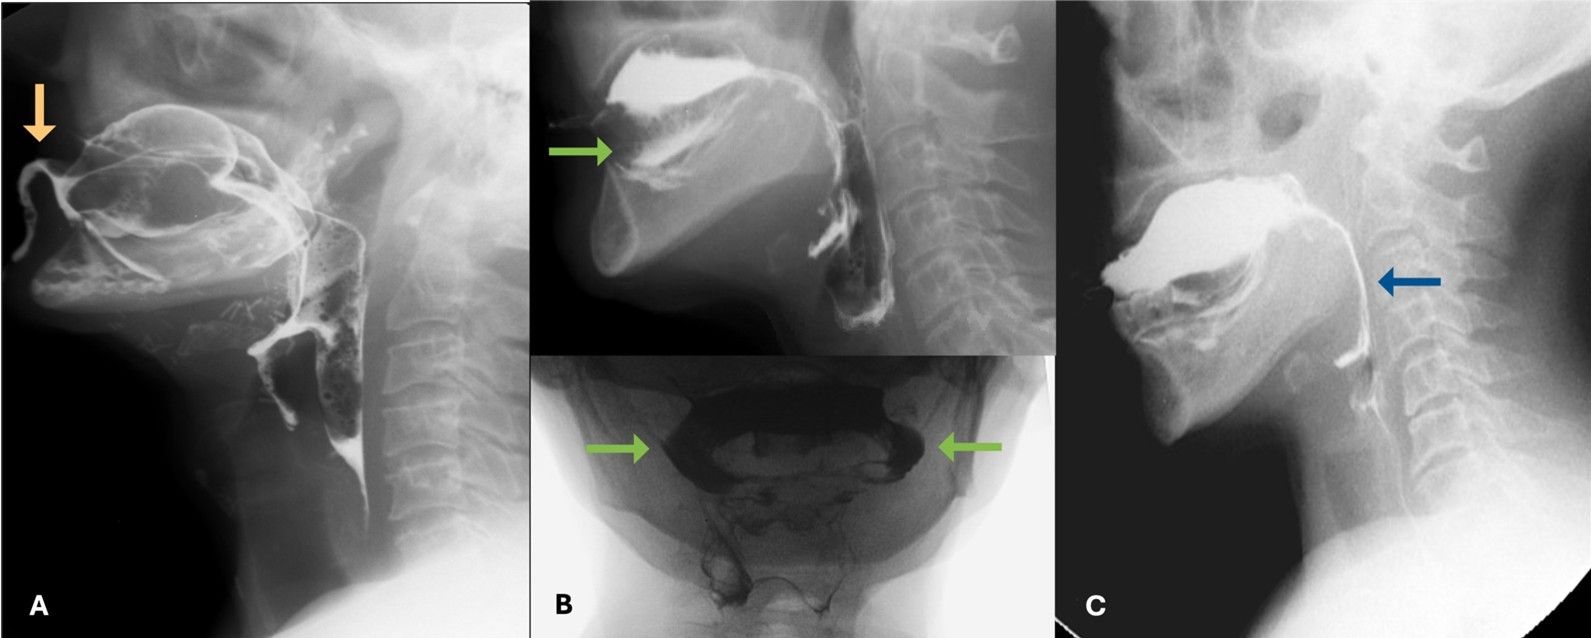

Defects in oral control of boluses are usually more apparent with liquid consistencies, especially thin liquids, as better muscular tonus is required for adequate management of this consistency. (Fig. 6)

Figure 6: Compromise of the oral control of boluses with anterior escape (orange arrow in A), lateral escape (green arrows in B) and posterior escape (blue arrow in C)